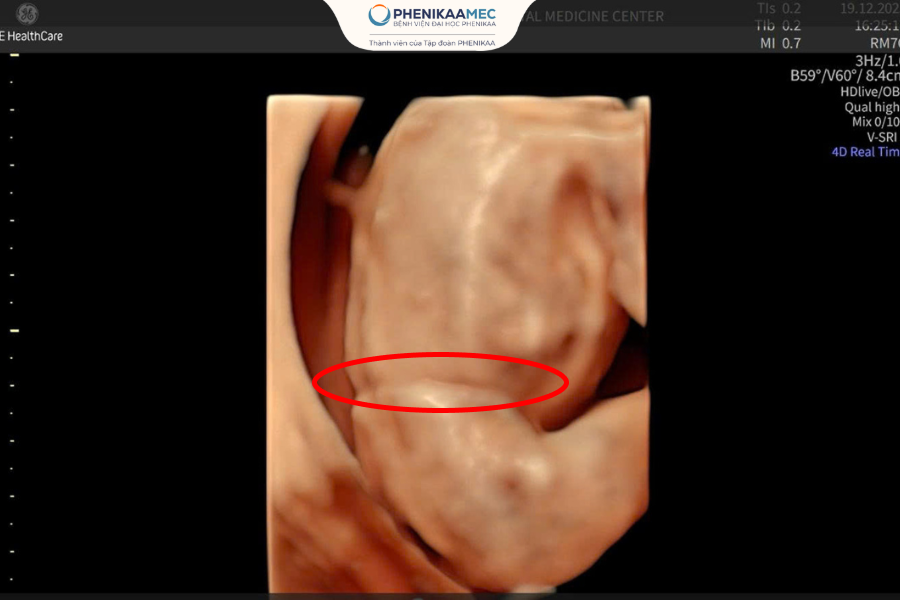

Vị trí dải xơ buồng ối trên hình ảnh siêu âm 4D

Quyết định này không được đưa ra một cách vội vàng. Trước đó, các bác sĩ đã đánh giá kỹ lưỡng vị trí dải xơ, mức độ ảnh hưởng đến thai nhi cũng như những rủi ro tiềm ẩn nếu tiến hành can thiệp. Khi mọi yếu tố được cân nhắc đầy đủ, phương án an toàn nhất lại chính là tiếp tục theo dõi.